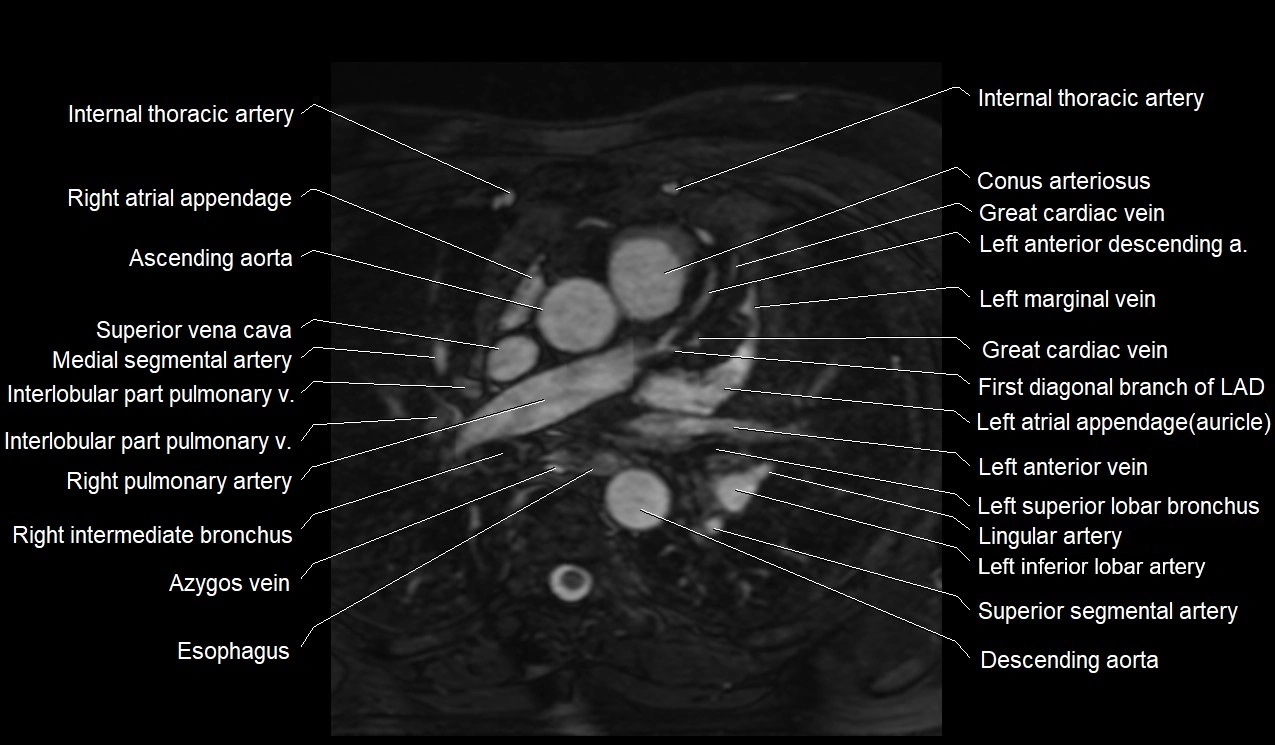

MRI image